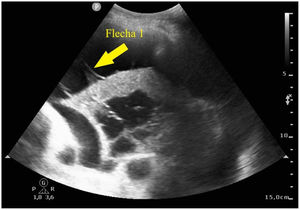

Paciente de 52 años con antecedente personal de síndrome de inmunodeficiencia adquirida, que ingresa en nuestra unidad por neumonía adquirida en la comunidad por Streptococcus pneumoniae. En la radiografía de tórax se objetiva infiltrado basal derecho y se realiza tomografía computarizada de tórax con hallazgos de neumonía necrotizante con probable absceso pulmonar incipiente. Presenta mala evolución, con hipoxemia refractaria a ciclos de prono, realizándose ecografía pulmonar. Se observa derrame pleural con trayectos fibrosos hiperecogénicos o signo del plancton en su interior (fig. 1, flecha 1), infiltrado basal derecho con hiperecogenicidad del parénquima por hepatización del mismo con broncograma aéreo, también interno (fig. 2, flecha 2), así como zonas trabeculadas hipoecogénicas bien delimitadas, compatible con neumonía necrotizante y absceso pulmonar (fig. 2, flecha 3).